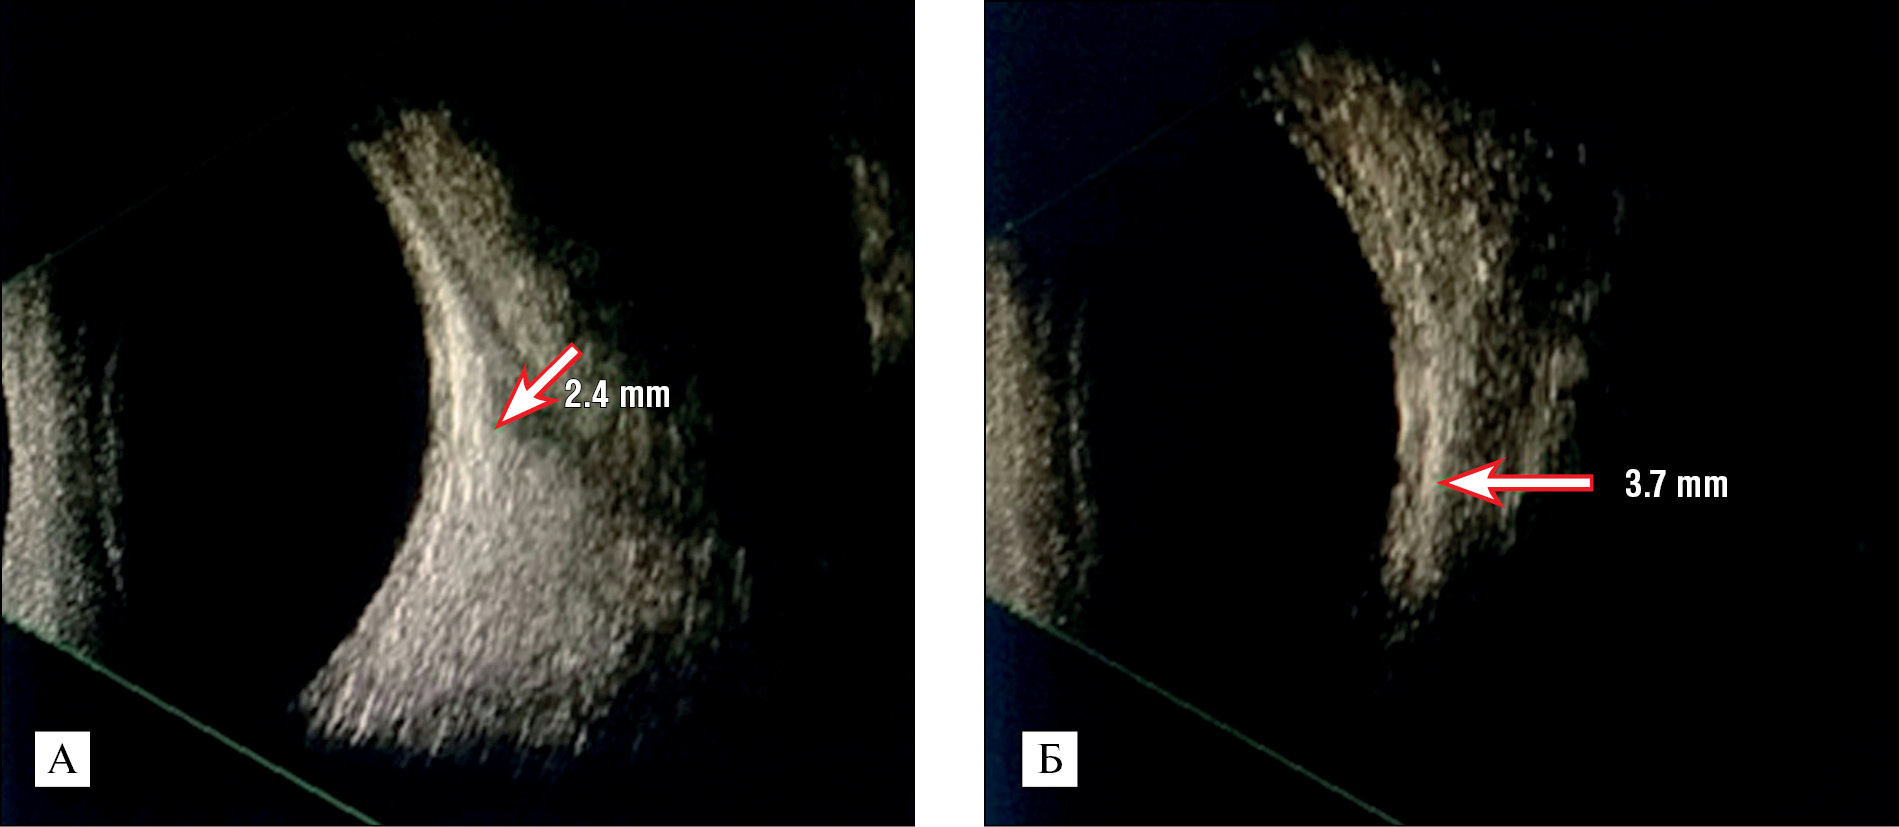

У детей II группы: при сходящемся косоглазии толщина ВПМ была равна 3,7±0,1 мм, толщина НПМ — 3,0±0,3 мм, при расходящемся косоглазии толщина НПМ составила 3,8±1,12 мм толщина ВПМ — 3,2±0,11 мм. На рис. 1 представлены сканограммы ЭОМ.

Рис. 1. Сканограммы глазодвигательных мышц (глазные мышцы визуализируются в виде трубчатых гипоэхогенных полос) А — внутренняя прямая мышца. Б — наружная прямая мышца.